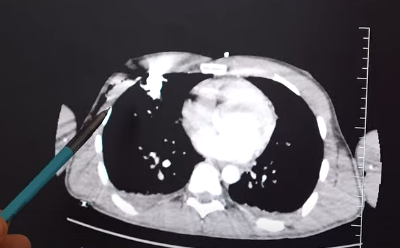

Наш пациент упал на арматуру. Скорая помощь доставила его в Склиф вместе с металлическим стержнем в корпусе.⠀

Специалистам Института Склифосовского предстояло извлечь 60-сантиметровый железный стержень из тела 23-летнего пациента.

Молодой человек оказался везунчиком - инородное тело, несмотря на размер, не задело жизненно важные органы.

Арматура незначительно повредила лёгкое и прошла через мягкие ткани. Тем не менее, находилась в опасной зоне, где расположены сердце и крупные сосуды.

В операционной работали сразу две хирургические бригады, чтобы не допустить кровотечения при удалении. Операция прошла успешно и пациента уже выписал